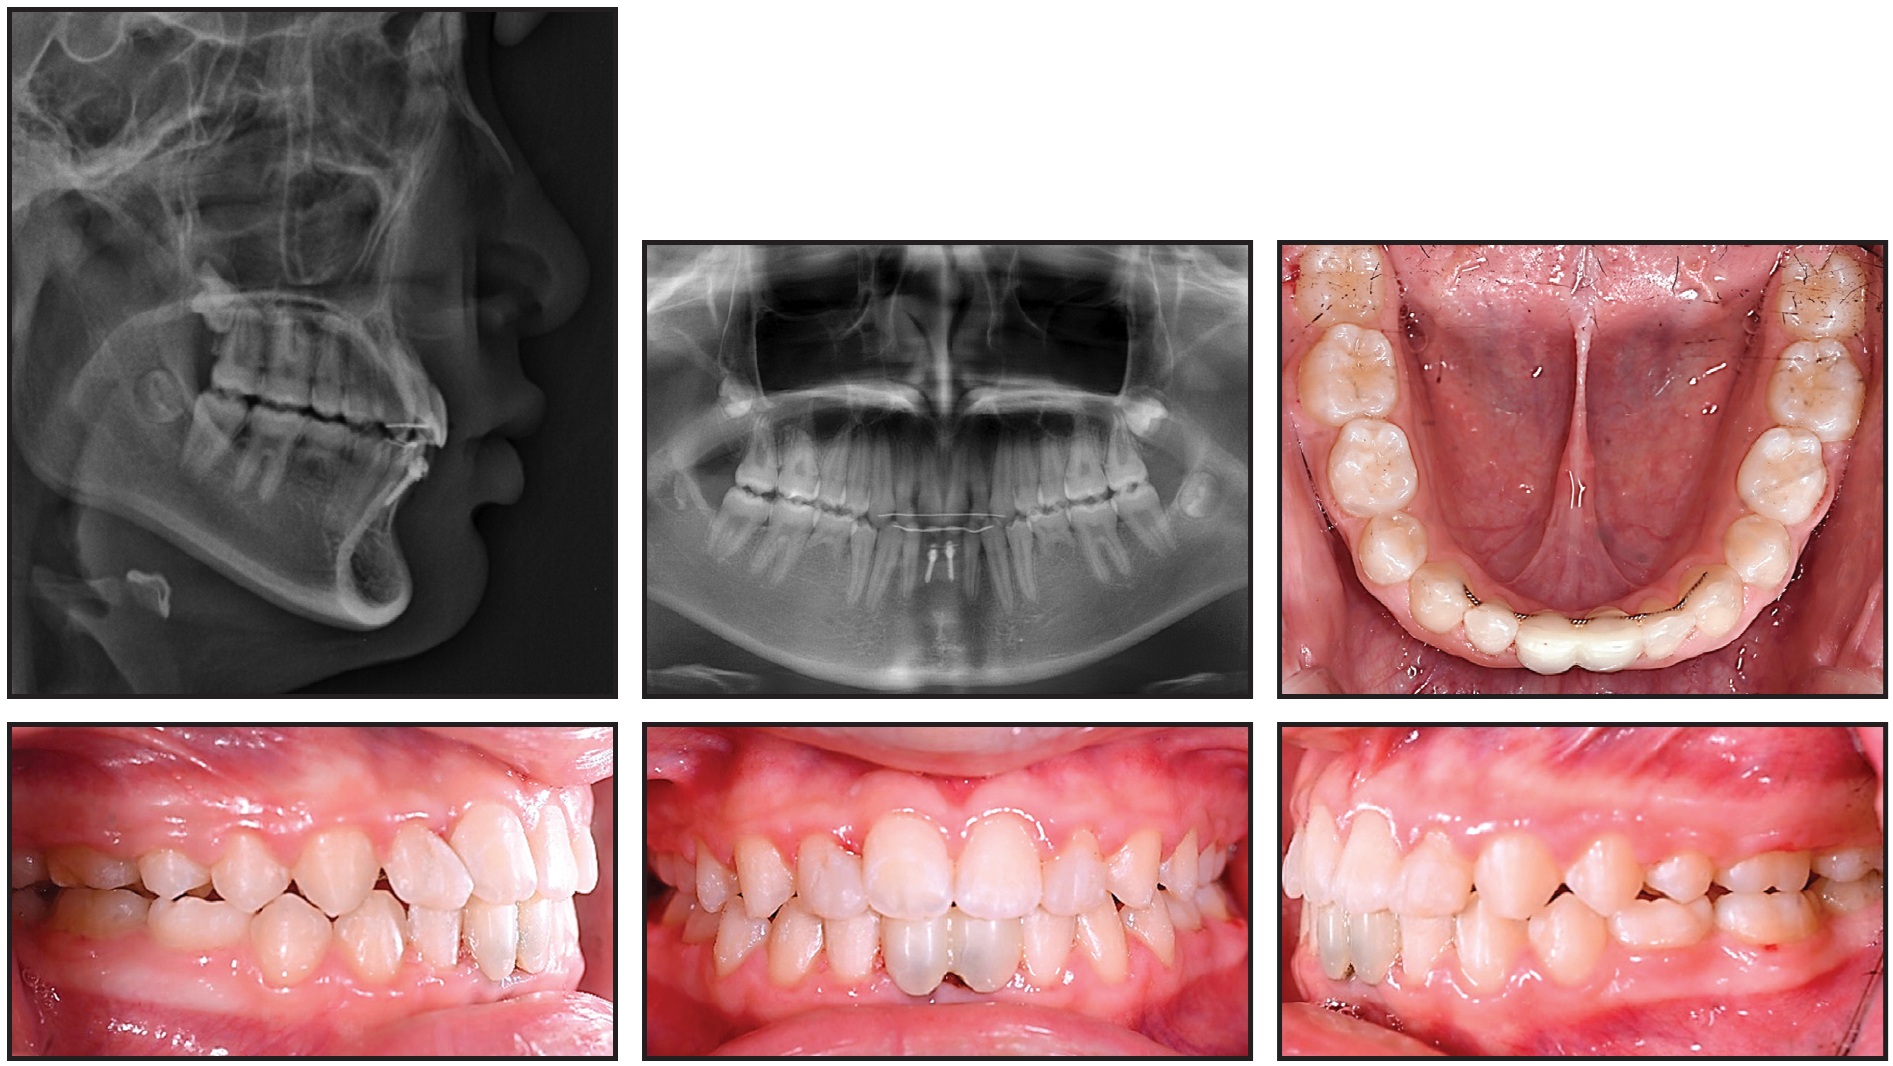

One year later, the patient exhibited a stable occlusion with Class I canine and molar relationships and favorable jaw growth (Fig. 10).

Fig. 10 A. Patient one year after treatment. B. Superimposition of pretreatment and seven-months-post-treatment cephalometric tracings.